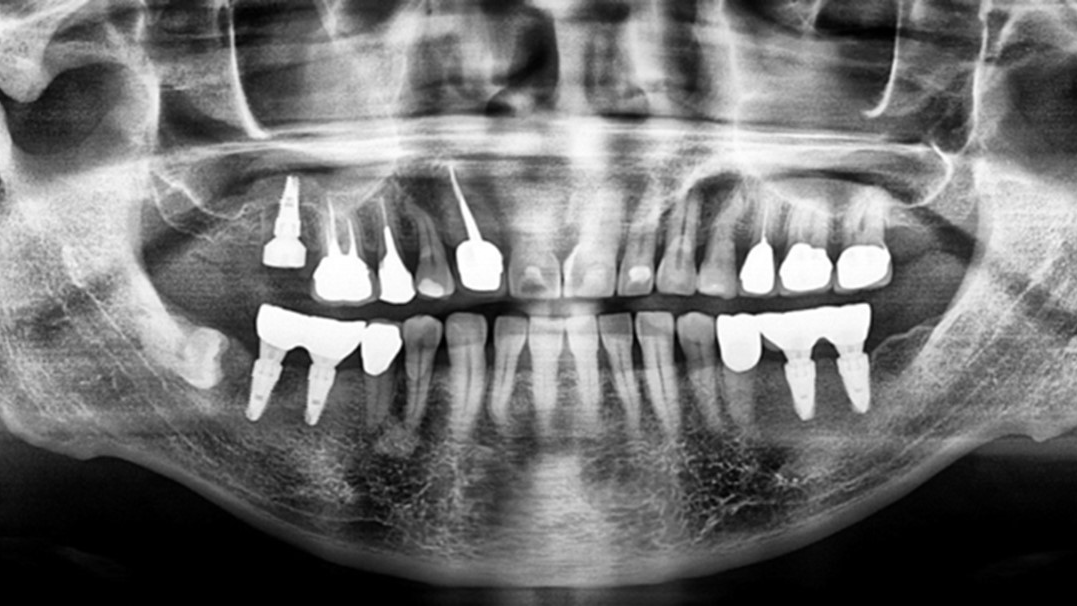

Complete Digital Workflow for Mandibular Full-arch Implant Placement and Temporalization by “Smile in a Box”

Abstract Modern oral implantology requires comprehensive diagnosis, intricate planning, and precise execution to achieve desired prosthetic and functional outcomes to meet patients’ and clinicians’ expectations. In this context, digital dentistry has been adopted as an excellent service, especially for complicated full-mouth rehabilitation cases, to which the implant all-on-6 concept has become an established treatment option. … Read more